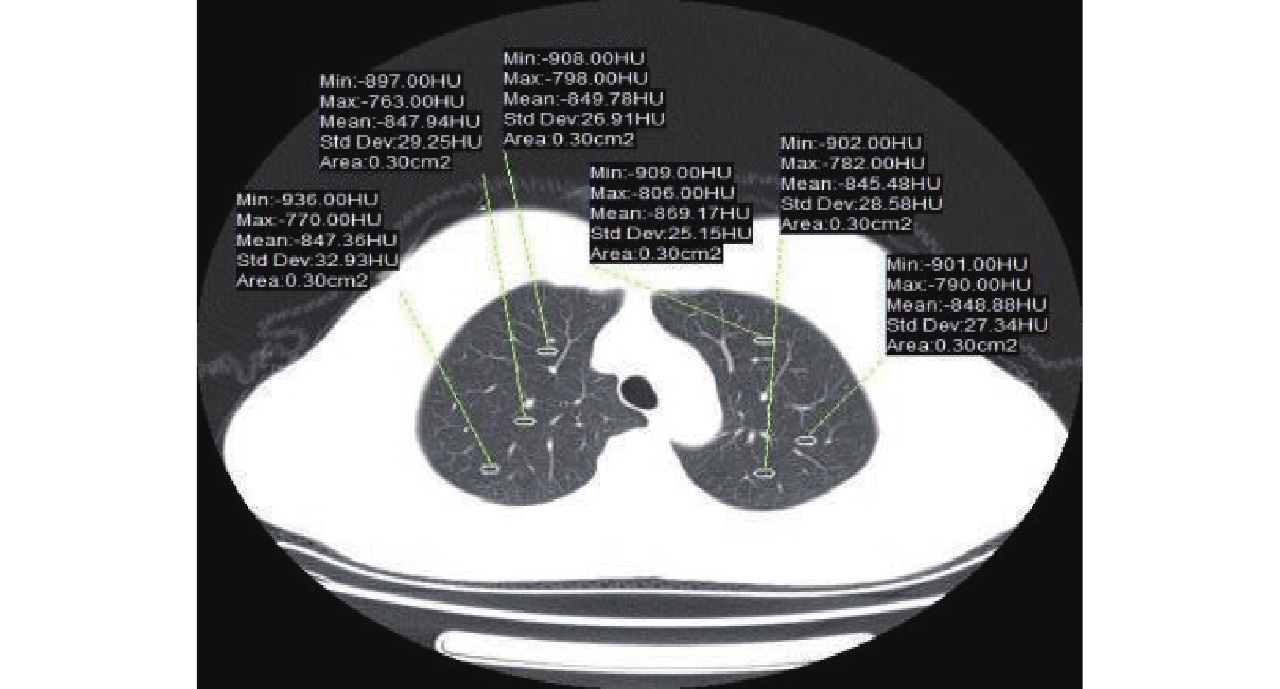

Table 4 The objective evaluation between the two groups

分组及检验 CNR SNR 低剂量组 28.83±2.95 30.62±3.10 常规剂量组 28.98±2.48 30.69±2.46 Z -0.851 -0.673 P 0.395 0.501 -